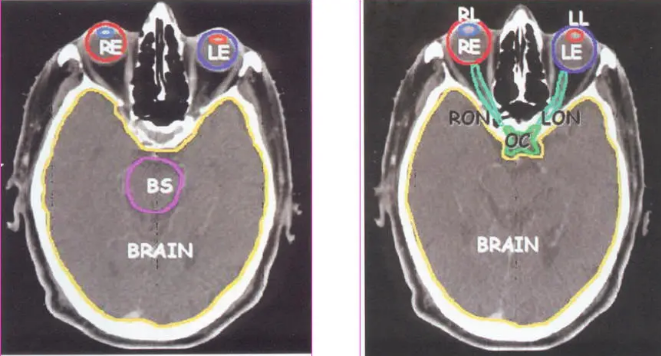

危及器官勾画:

通常需要勾画的危及器官有:脑干、晶体、视神经、腮腺、脊髓、肺、心脏、肝、肾、小肠、膀胱、直肠等,因为这些组织和器官严重受损将会给病人带来严重后果。